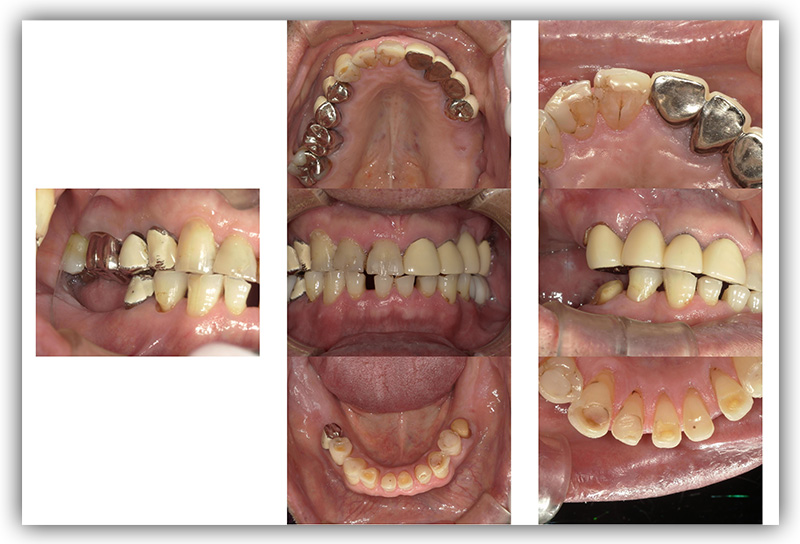

CASE_03

40代女性(インプラント)

- 40代 女性

- 被せものをインプラントにしたい

- 2箇所

- インプラント

- 84万円

- 約半年

- 治療期間がながい、外科的治療が必要